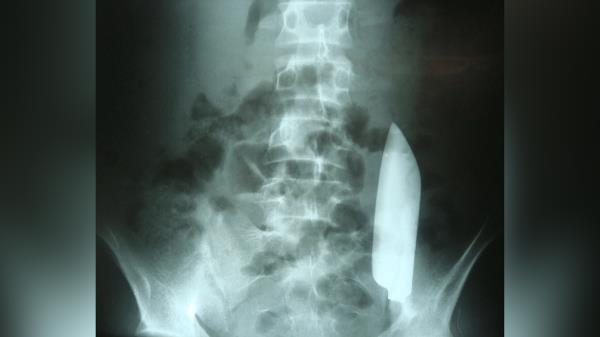

一名男子腹部的刀片神秘地“漂浮”到身体的另一边,却没有造成伤害